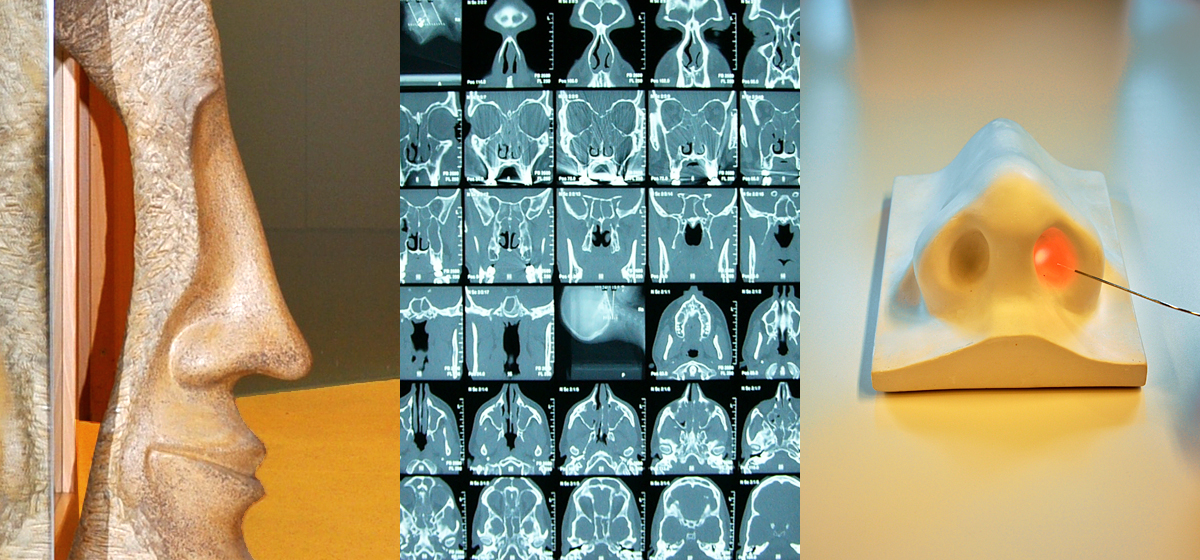

Rhinologie / Rhinochirurgie / Plastische Nasenchirurgie

Behandlung von Behinderungen der Nasenatmung mit verschiedenen Ursachen und damit verbundenen Krankheitserscheinungen wie

• Chronische Erkrankungen der Nasennebenhöhlen, Nasenpolypen

Häufige Ursache für eine Atmungsbehinderung der Nase ist eine schief stehende Nasenscheidewand (Septumdeviation), die den Luftfluss in der Nasenhaupthöhle negativ beeinflusst und langfristig auch eine dauerhafte Schwellung der inneren Schleimhautstrukturen verursachen kann. Auch Allergien, Heizungsluft und ein gestörter Flüssigkeitshaushalt in den Schleimhäuten wirken nachteilig auf die nasale Atemfunktion ein. Insbesondere der häufige oder dauernde Gebrauch abschwellender Nasensprays verschlechtert die Situation nachhaltig.

Eine häufig erfolgreiche und operationsersetzende Methode stellt die Laserbehandlung der Nasenschwellkörper (Nasenmuscheln) dar, deren Anwendung ambulant und schmerzfrei möglich ist und in vielen Fällen angeraten werden kann.

Eine Besonderheit ist die plastisch-ästhetische Nasenoperation, die in der Hand des erfahrenen Rhinochirurgen funktionelle und ästhetische Aspekte gleichermaßen berücksichtigt und die Lebensqualität außerordentlich verbessern kann. In einem oder mehreren ausführlichen Beratungsgesprächen werden die Ziele eines solchen Eingriffs gemeinsam festgelegt und die Methoden eingängig und verständlich erläutert.

Alle nasenchirurgischen Eingriffe werden minimalinvasiv und unter Verwendung des Operations-Mikroskopes und von Endoskopen durchgeführt.